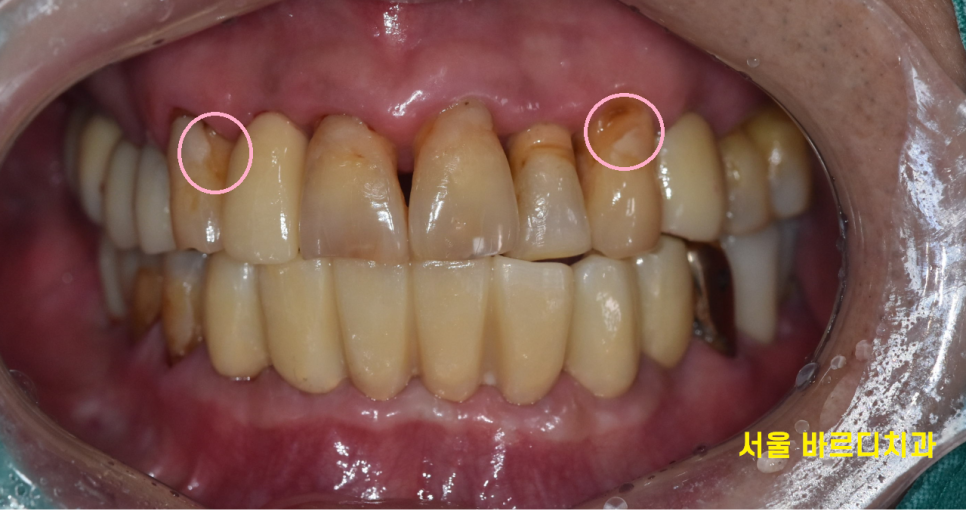

치아 불편감으로 저희 병원을 내원해주신 환자분입니다.

검사를 위해 찍어본 x ray

전형적인 풍치 증상입니다.

녹아버린 잇몸뼈로 치아가 흔들 흔들

길어 보이는 상황이었습니다.

양치도 전반적으로 안되어있어

치태라고 하는 찌꺼기들이 치아 전반적으로 붙어있었습니다.

구강위생이 불량하니 잇몸이 더 빨리 무너졌네요~~

기타 증상으로는 녹아버린 잇몸뼈로

잇몸이 위로 올라가다보니 치아 뿌리 부분이 노출

양치가 안되면서 뿌리부분이 썩고,

전반적으로 파여있는 모습이었습니다.